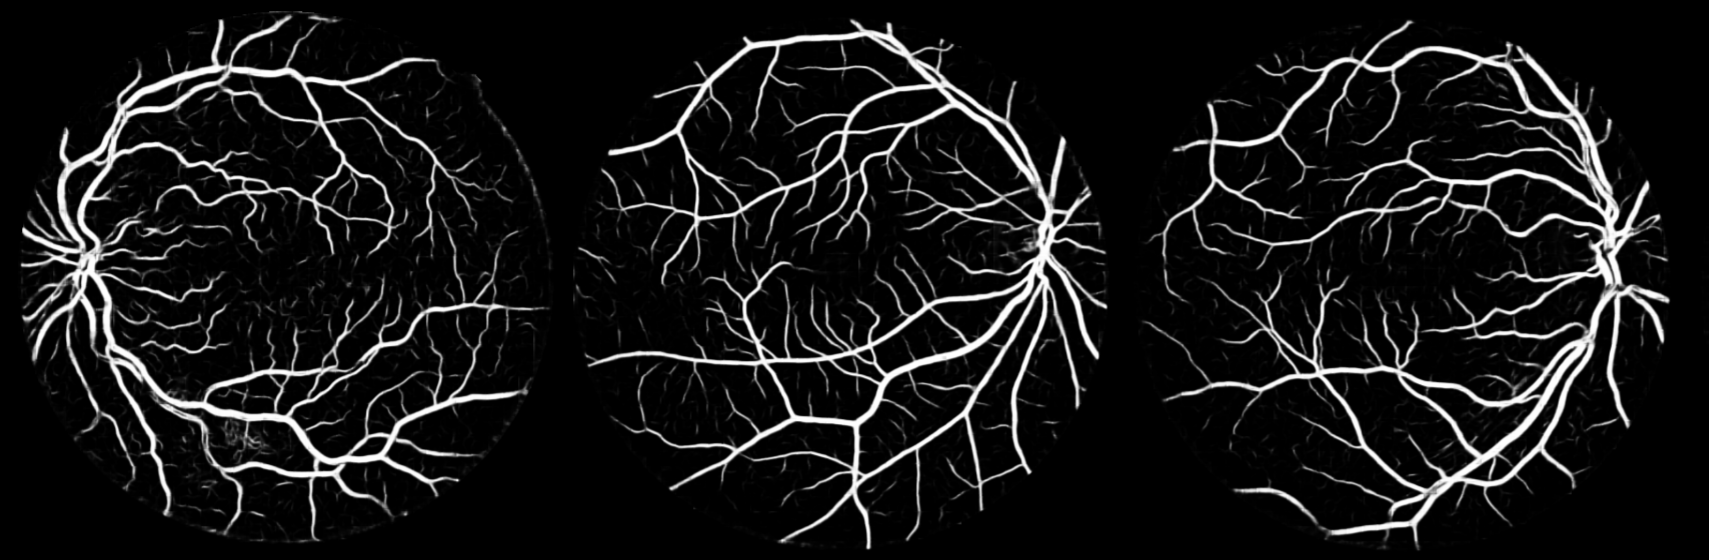

Fig. 3: Visualization of the prediction made by our proposed technique on three samples randomly taken from the DRIVE dataset: (a) Original preprocessed image (b) Corresponding ground truth and (c) Segmented output.

Fig. 3 shows the qualitative outputs of our proposed method. More visualizations of results and intermediate results can be found at project website 111https://avijit9.github.io/my_posts/FCN_Retina.html.